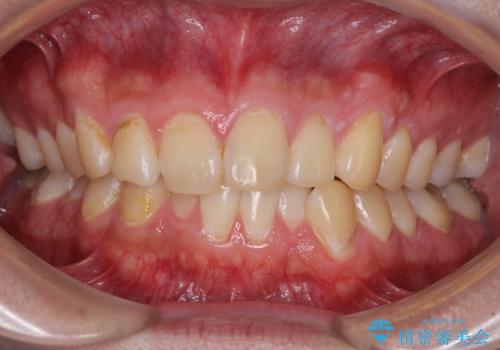

- 上下前歯のデコボコを気にして来院された患者様です。

前歯のデコボコ以外に左側の奥歯の咬み合わせに問題がありましたが、価格を抑え、短期間で気になる前歯を治したいとのことでした。

写真より左側臼歯の咬合がタイトではないことが分かりますが、こちらは保定期間に徐々に咬合させていくこととしました。